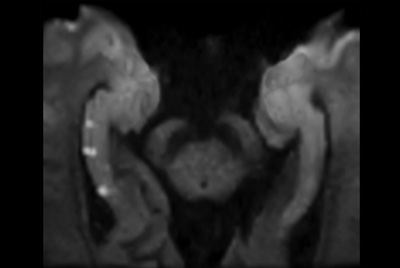

Prostate with dual coil set-up

Prostate with Vega HP gradients

Compressed SENSE Prostate imaging

Prostate with dS ZOOM imaging

High resolution Prostate imaging with Compressed SENSE

Prostate lesion with fat-free mDIXON XD imaging

Prostate lesion with high b-value DWI

Prostate imaging with motion reduction techniques

Prostate with Compressed SENSE on BlueSeal magnet

Prostate imaging with dS Endo + dS Torso coil

Prostate imaging

Multi-parametric MR of the prostate